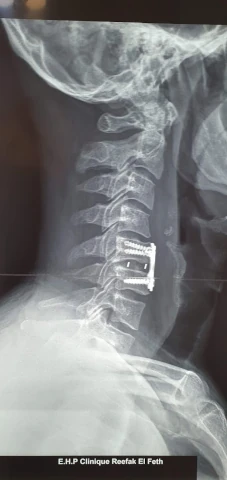

Galerie